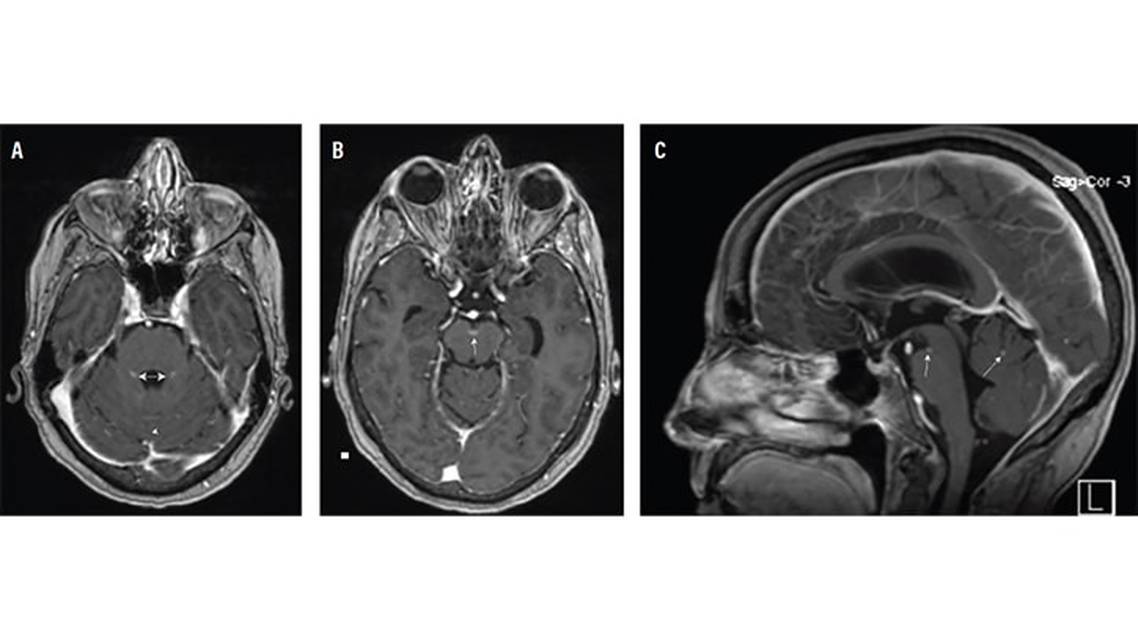

Repeat brain MRI with and without contrast in the last days of admission showed multiple foci of enhancement in the interpeduncular cistern and the cerebellum (Figure 1). Cytology results from the CSF came back with cells consistent with metastatic melanoma (Figure 2). Dermatology evaluation was pursued, leading to the biopsy of 2 cutaneous lesions, both of which were determined to be benign.